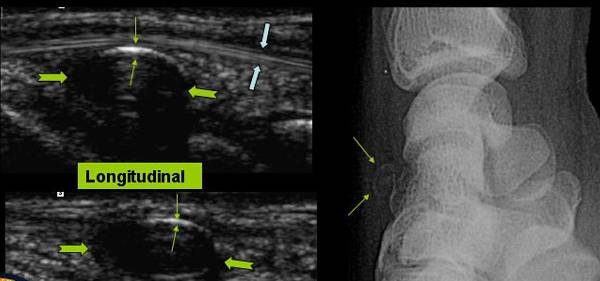

CHIST SINOVIAL CALCIFICAT INTR-UN SANT TENDINOS

Tumefactie sensibila pe fata dorsala a pumnului

Mica structura chistica → cu contur partial calcificat → in contact cu extensorul degetului 4 →